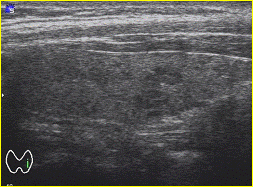

При подозрении или наличии тиреоидной патологии

выполняется следующий спектр исследований: определение уровня гормонов в крови

(ТТГ, свТ4, св Т3, ат к ТГ), ультразвуковое исследование щитовидной железы с

использованием допплерографии и сонографии, сцинтиграфия щитовидной железы,

пункционная биопсия под контролем УЗИ (рис. 1) с последующим цитологическим

исследованием. Пункция щитовидной железы выполняется непосредственно врачом

эндокринологом.

Рисунок 1. Методика проведения

пункционной биопсии